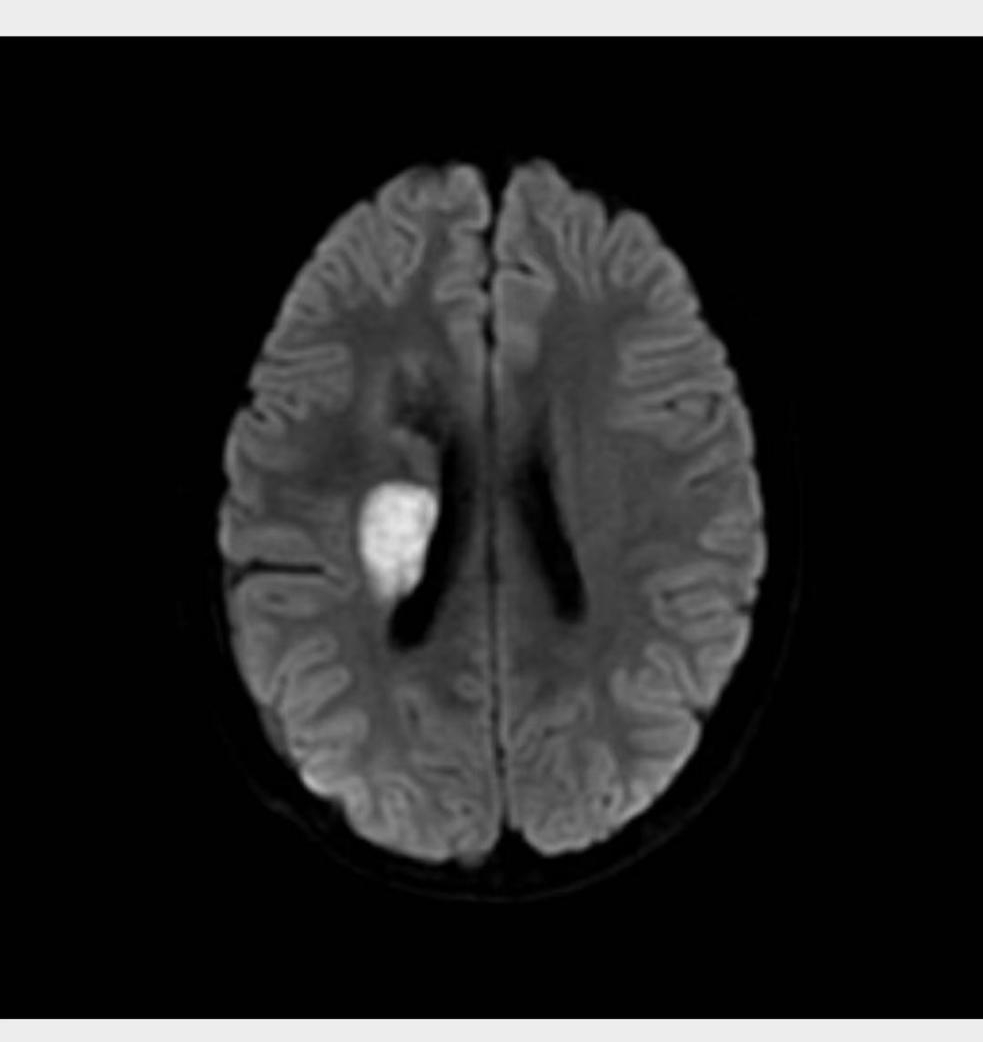

图为李平脑梗后的核磁共振检查

一个月前 , 家住安康汉滨区李先生15岁双胞胎儿子的弟弟李平(哥哥李军 , 均为化名)正在学校食堂吃饭 , 突然眼前一黑摔倒在地 , 左侧肢体无力 , 言语含糊 , 头晕头痛 。 急诊送入安康市第一人民医院 , 诊断为“右侧大面积脑梗死” , 溶栓治疗后效果差 , 左侧肢体仍无法活动 , 言语含糊 。 为了进一步治疗到交大一附院神经内科 , 颅内血管造影正常 , 相关医生找到结构性心脏病科张玉顺主任 , 经过MDT会诊后 , 得出了“先天性心脏病”是元凶的结论 。